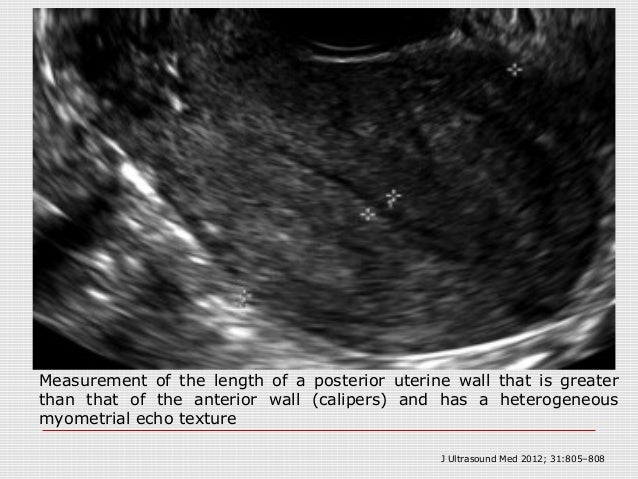

What does a heterogeneous uterus mean-–808 807 Sakhel and Abuhamad—Sonography of Adenomyosis Figure 5 Measurement of the length of a posterior uterine wall that is greater than that of the anterior wall (calipers) and has a heterogeneous myometrial echo texture Figure 430/8/ The endometrium is the lining of the uterus The endometrium is well seen on ultrasound exams and it's thickness is usually measured It is seen a stripe that is brighter than the surrounding uterine tissue it usually appears smooth and of similar consistency throughout In patients who are postmenopausal the thickness cutoff for abnormal is